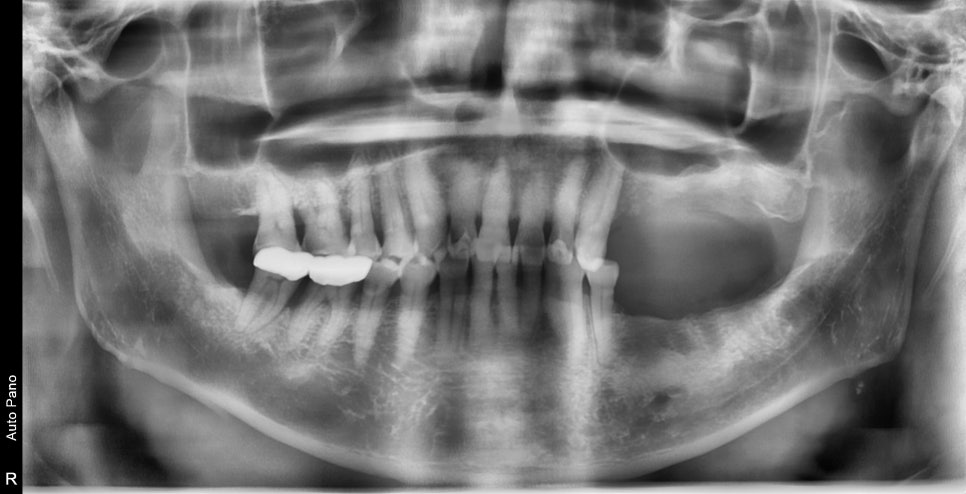

23.04.25 — 치료 전

CT와 파노라마 분석 결과, 치아 뿌리 끝에 염증이 생긴 상태였고 잇몸뼈까지 녹아내리는 만성 복합치주염이 함께 진행되고 있었습니다. 남은 뼈와 잇몸을 지키기 위해 발치를 먼저 진행했습니다.